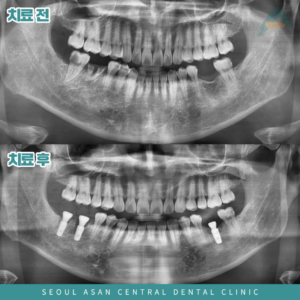

성남치과 심한 치주염으로 치아를 상실하게 된다면

성남치과 심한 치주염으로 치아를 상실하게 된다면 <상실된 치아는 빠른 치료가 필요한 이유> 혹시 평소에 잇몸이 자주 붓거나 피가 나거나, 또는 시린 증상이 반복적으로 나타나고 있지 않으신가요? 만약 이런 증상이 자주…